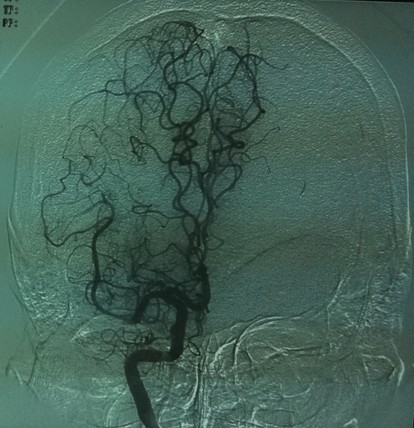

35mg r-tPa溶栓后见右侧颈内动脉开通,大脑前及大脑中动脉显影良好